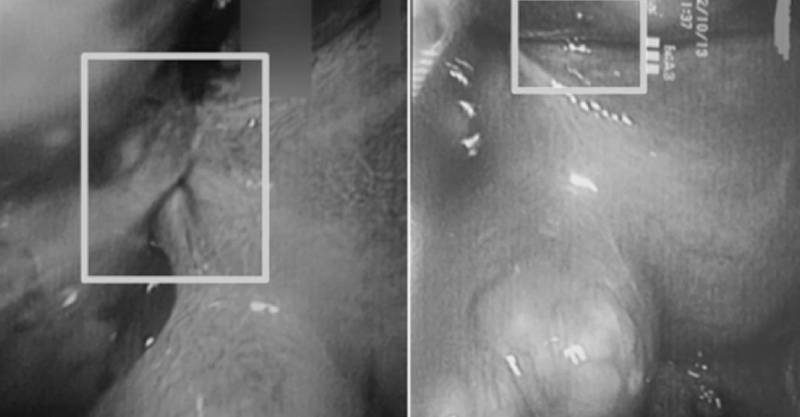

根據《TVBS新聞網》、《ETtoday健康雲》報導,王姓女病患肚子痛了一整晚,持續腹痛讓她嘔吐不止、痛到蜷縮,以為是闌尾炎緊急送醫。結果超音波檢查發現王女肚臍下方有一顆約8公分大的子宮肌瘤產生扭轉變形狀況,緊急接受腹腔鏡手術,最終切除5顆肌瘤。

翻攝自萬芳醫院提供畫面。

診治王姓女病患的婦產科醫師張宇琪說明,30歲以上女性幾乎每5人就有1人罹患子宮肌瘤,但常見個案多為良性腫瘤,定期追蹤有無增長病變即可。這次女病患身上的肌瘤扭轉相對少見,會出現急性腹痛、噁心嘔吐等症狀,扭轉嚴重導致組織缺血壞死的話更會發燒畏寒。扭轉狀況多發生於漿膜下蒂的肌瘤,若大小超過5公分、蒂長又細或是病患懷孕時,發生機率則會提高。